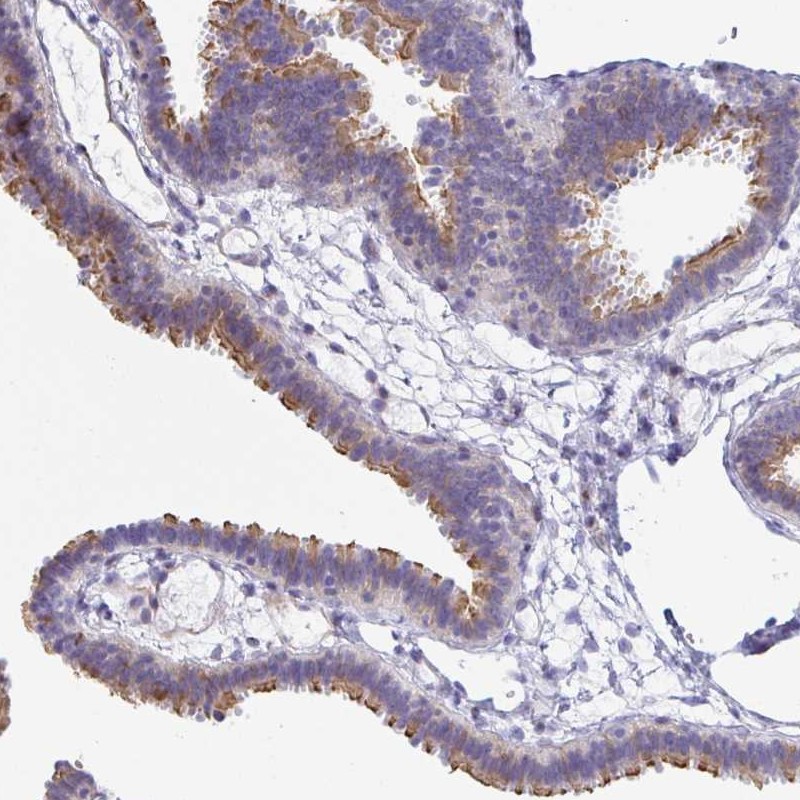

Immunohistochemical staining of human fallopian tube shows strong positivity in cilia.